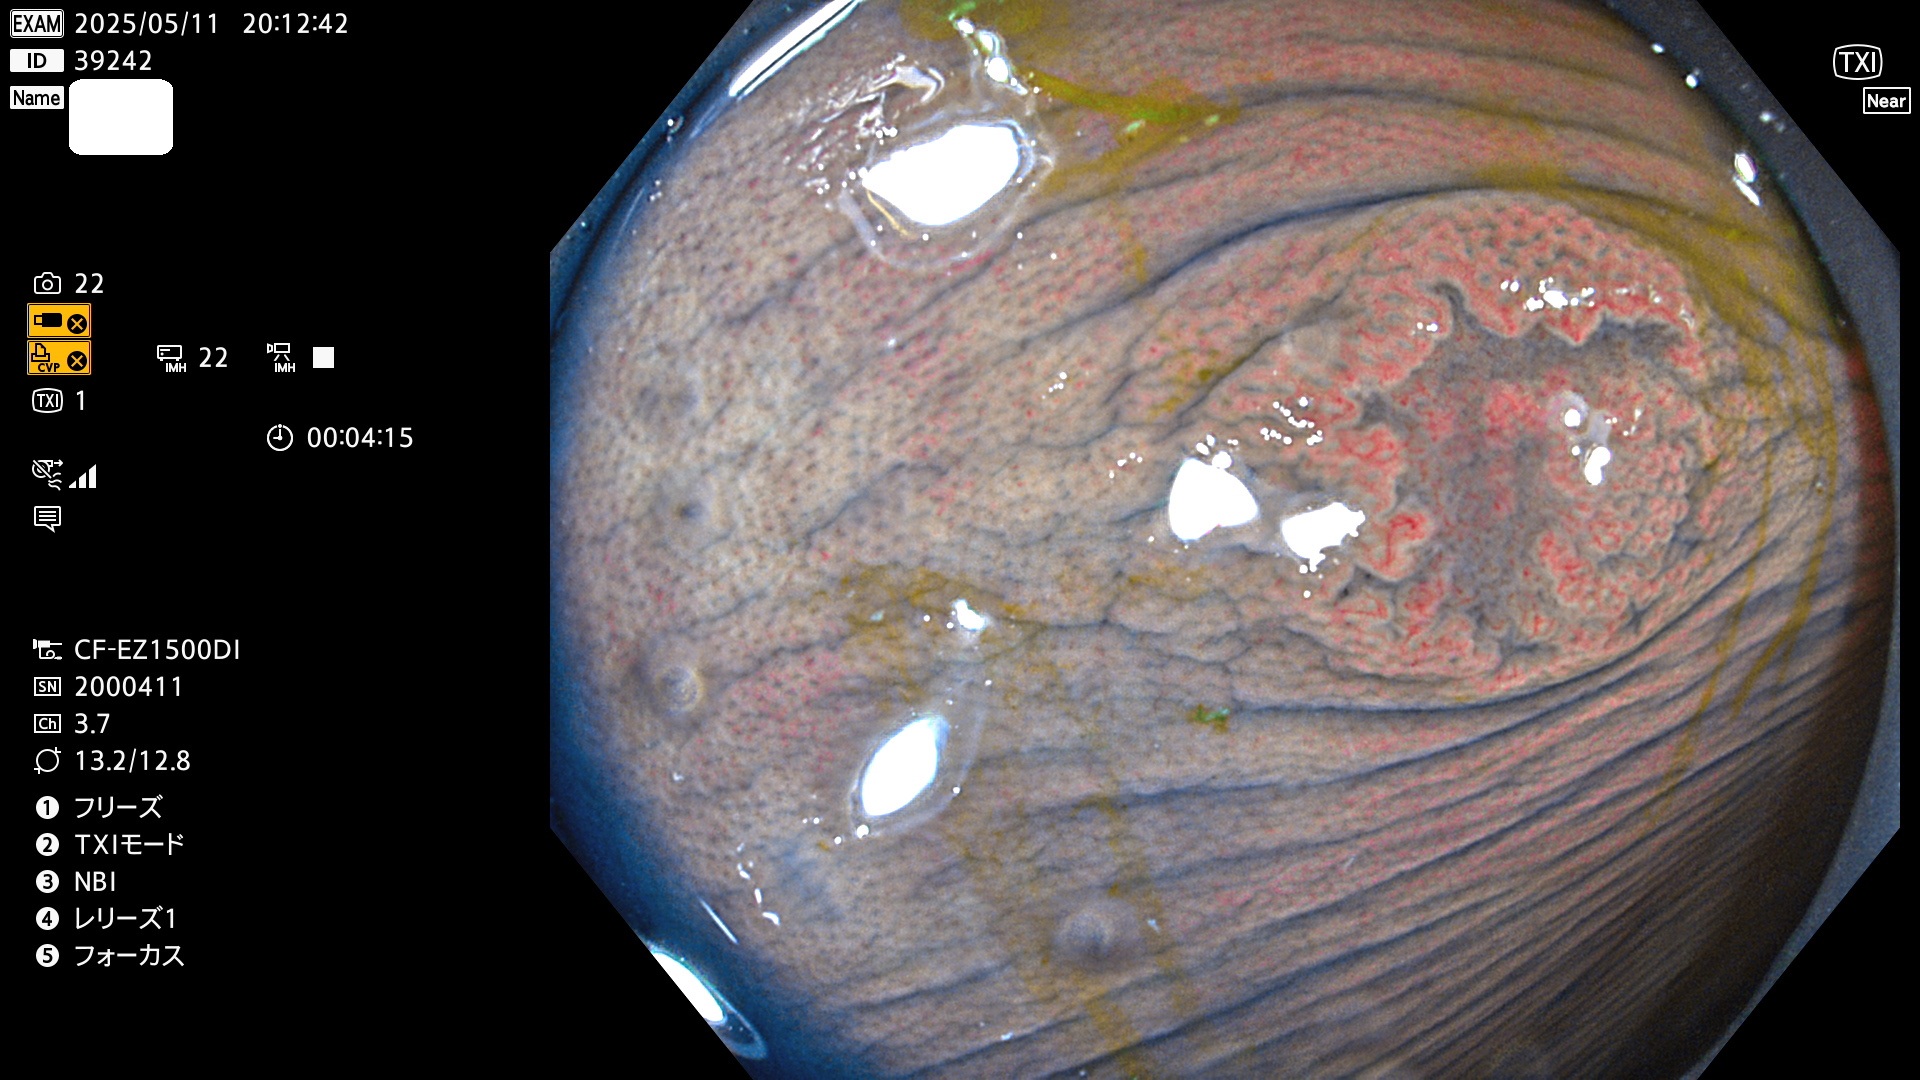

完全に平坦な物をUb、陥凹している物をUcと呼びます。Ubは認識が困難で、Ucはびらん(炎症)と紛らわしいために見落とされやすく、「内視鏡後・大腸癌」の原因になります。

抽出の対象期間 2025年5月8日〜5月11日の4日間(48件の検査)14個 (14/48=29%)